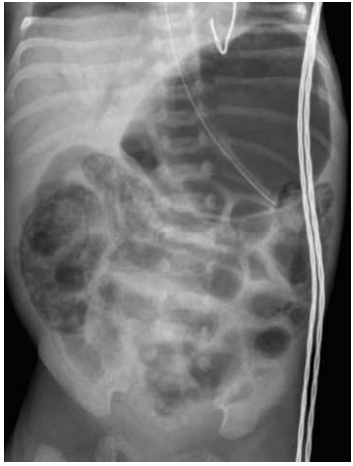

A enterocolite necrosante (NEC), mostrada na figura abaixo, é uma doença de origem desconhecida que afeta principalmente recém-nascidos prematuros (80% dos casos). As manifestações cobrem amplo espectro, de distensão abdominal leve com hematoquezia a choque séptico fulminante com necrose transmural de todo o trato gastrointestinal. Com relação a essa patologia, analise as afirmativas a seguir.